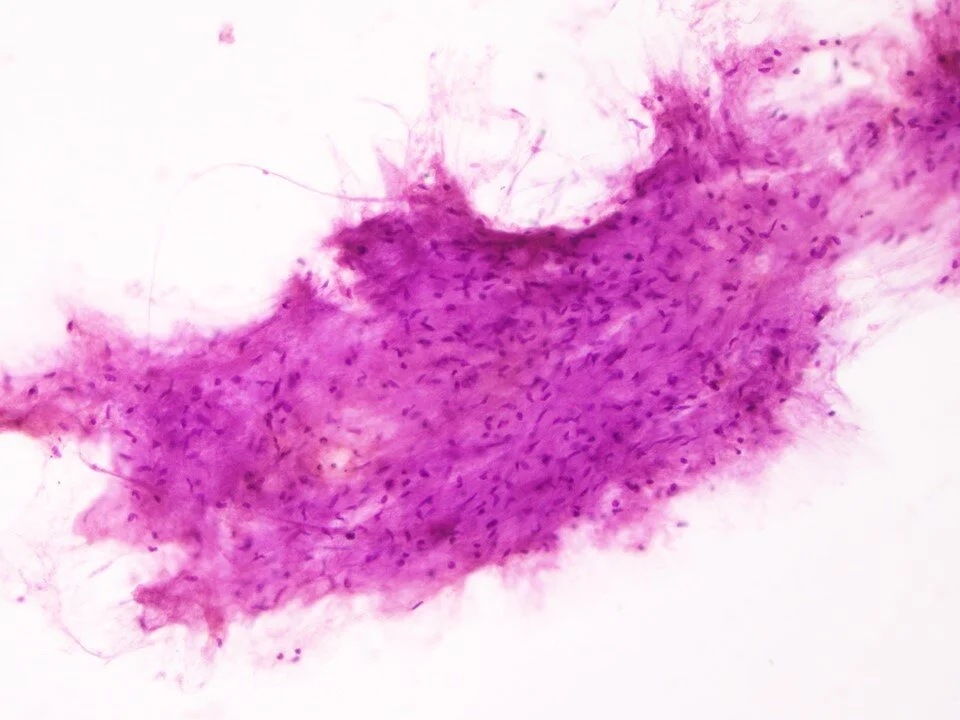

Sclerosing pneumocytoma

Sclerosing pneumocytoma - cell block